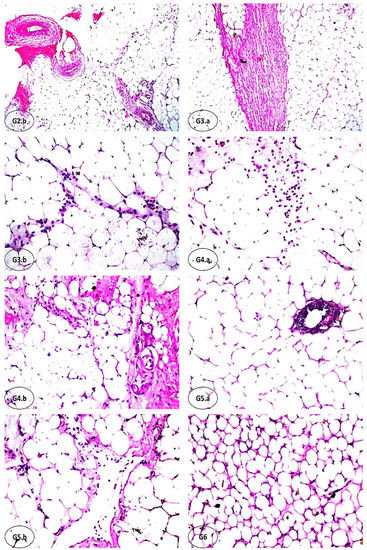

3.7. Effect of FCM, FCM-D, and IF on Histopathological Alterations of Adipose Tissues